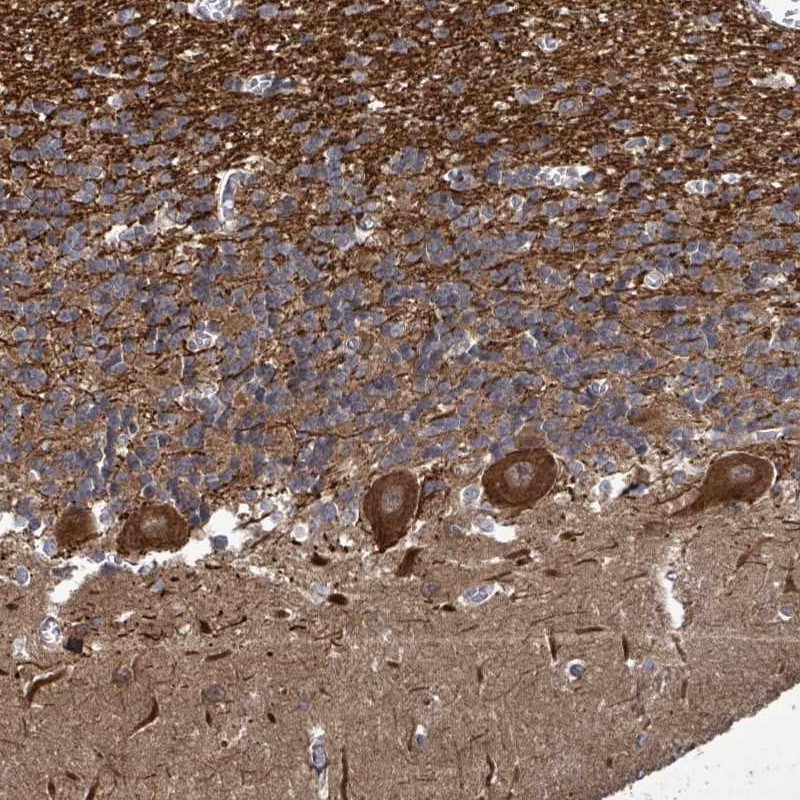

Immunohistochemical staining of human cerebellum shows strong cytoplasmic positivity in Purkinje cells.